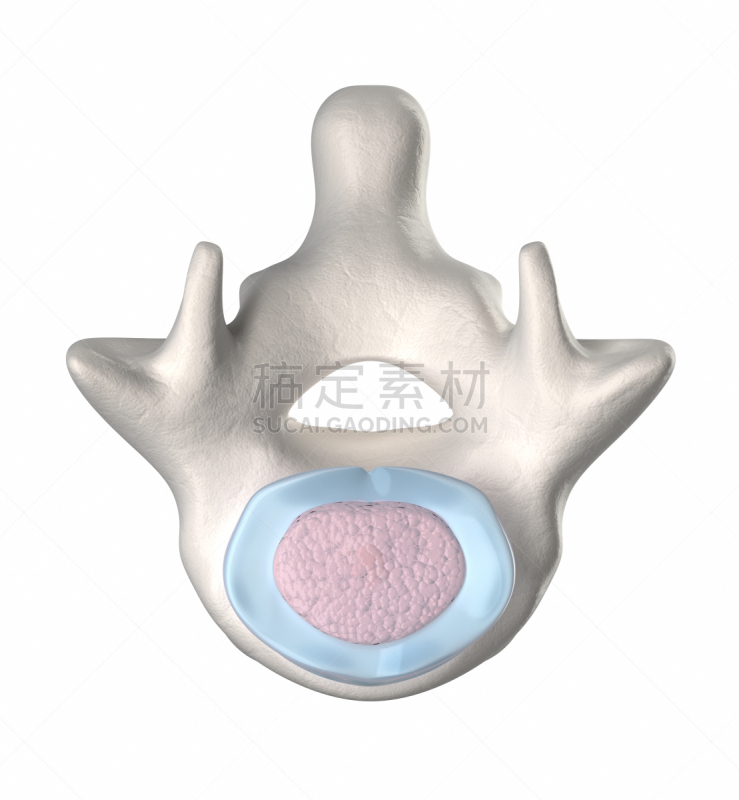

人体椎间盘横截面详情

JPG